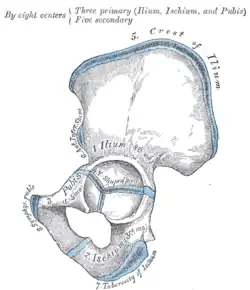

![]() Overview of Ilium as largest bone of the pelvis | |

Plan of ossification of the hip bone